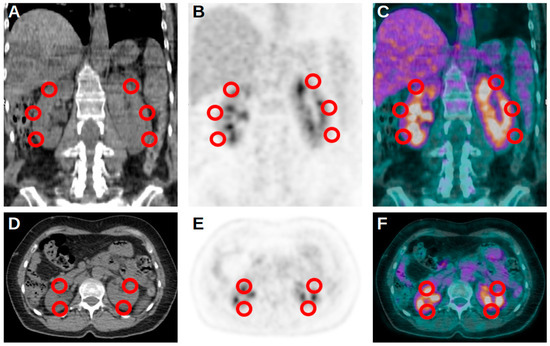

- Kidera, E.; Koyasu, S.; Hayakawa, N.; Ishimori, T.; Nakamoto, Y. Association between diffuse renal uptake of 18F-FDG and acute kidney injury. Ann. Nucl. Med. 2022, 36, 351–359. [Google Scholar] [CrossRef] [PubMed]